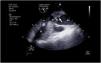

During cannulation, using ultrasound, we can check the intravascular insertion of the guides and subsequently of the cannulas. In the case of using a double-lumen cannula, transesophageal echocardiography (TEE) is essential, since serious complications may occur during implantation (perforation of the RA or cava superior, migration towards the RV), and we must check the correct orientation of the return flow towards the tricuspid valve.21 In cannulation with a simple double cannula, we can use transthoracic echocardiography (TTE) or TEE in the absence of a good acoustic window. When using the femoral-jugular configuration, the draining cannula must be located in the inferior cava below the left suprahepatic vein, and the tip of the return cannula must be positioned at RA level (Fig. 2) (Supplementary material 3). In the femoral-femoral configuration, the draining cannula should be positioned in the inferior cava and the return cannula in the RA. The distance between the two cannulas should be at least 10 cm to avoid recirculation.